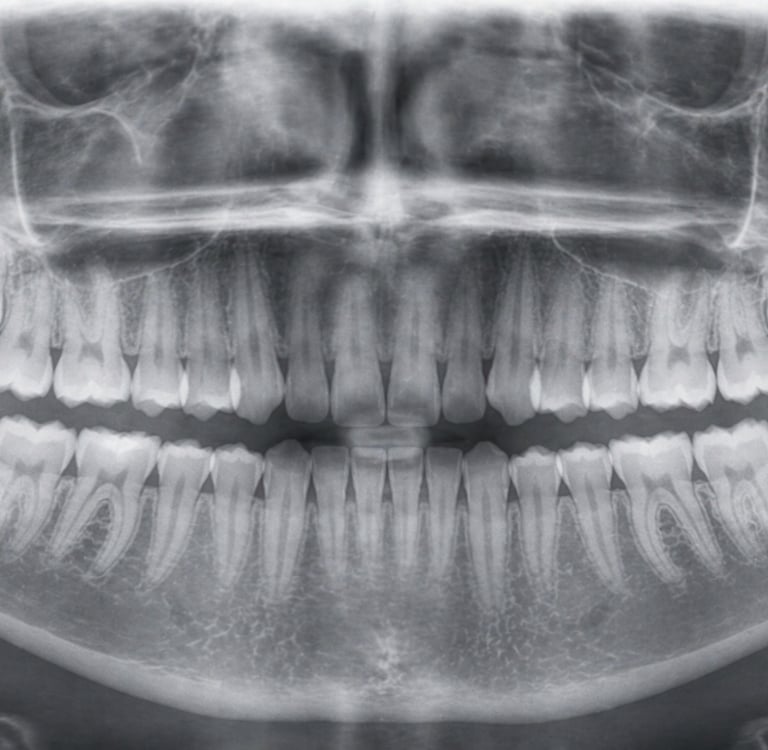

Queixals del seny inclosos o mal posicionats

Extracció dels queixals del seny

Dents inclosos o parcialment erupcionades.